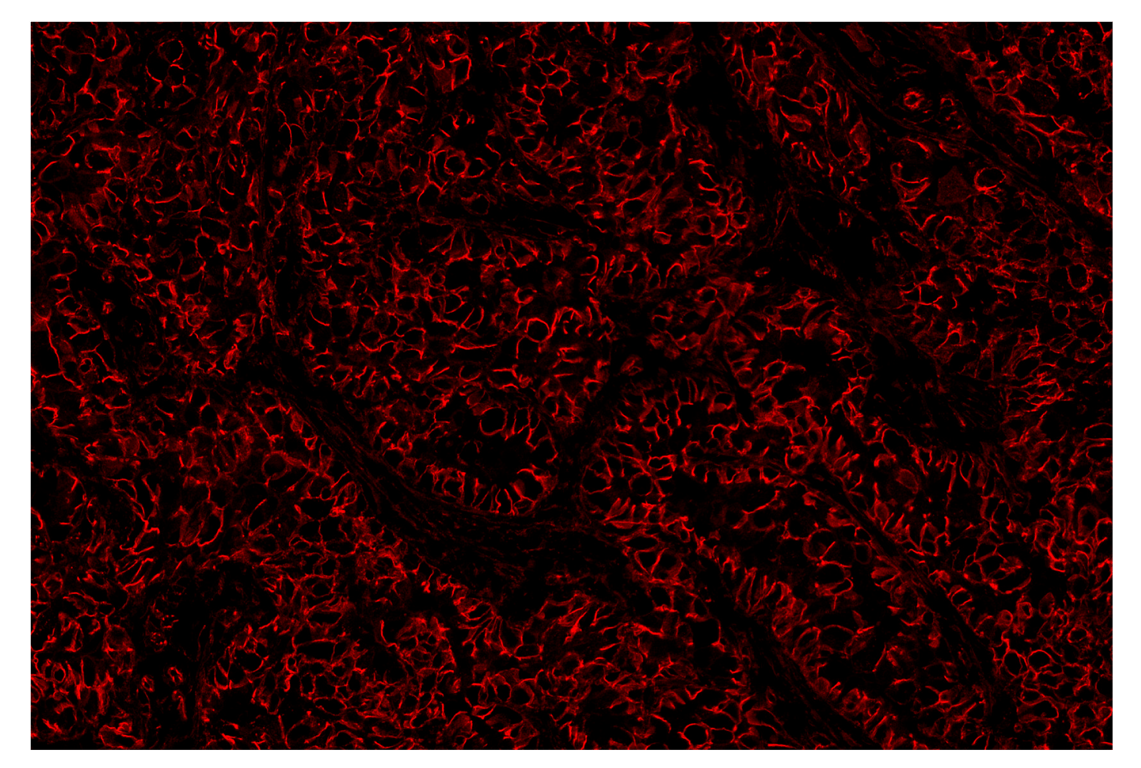

SignalStar™ multiplex immunohistochemical analysis of paraffin-embedded human lung adenocarcinoma using β-Catenin (D10A8) & CO-0108-647 SignalStar™ Oligo-Antibody Pair #25901 (red). All fluorophores have been assigned a pseudocolor, as indicated. Staining was performed on the BOND RX autostainer by Leica Biosystems.

Immunohistochemistry Image 3: beta-Catenin (D10A8) & CO-0108-750 SignalStar<sup>™</sup> Oligo-Antibody Pair